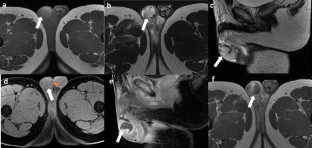

Intratesticular hematoma is one of the most frequent presentations of scrotal trauma. Ultrasound is the first-line imaging modality in the evaluation of scrotal trauma, and its findings are crucial for the choice of treatment. An intratesticular hematoma may represent a diagnostic pitfall for the investigating physician since its appearance may mimic other conditions, such as testicular neoplasms or segmental infarction. Although the gold standard imaging modality for the characterization of a testicular lesion is contrast-enhanced magnetic resonance (MR), MR equipment is not always available in an emergency department. Contrast-enhanced ultrasound (CEUS) may represent a valid and cheaper alternative compared with MR, which may aid the physician in the differential diagnosis. We describe the case of a 19-year-old male with a scrotal trauma following a motorcycle crash. In accordance with the literature, we carried out a contrast-medium whole-body computed tomography for the evaluation of any potential traumatic injury. Because of scrotal swelling and the patient complaining about pain in the right testicle, we performed a scrotal ultrasound, which demonstrated an enlarged right testicle, with an inhomogeneous echostructure due to the presence of a hypoechoic area in the middle and upper portion of the testicle. Color Doppler ultrasound did not show signals of intralesional vascularization. The lesion, although having characteristics compatible with hematoma, must not be diagnosed as testicular neoplasia, segmental infarction, or other mimics. For more information, a CEUS examination was performed. The examination clearly showed the extent of the lesion, the integrity of the testicular capsule, and the absence of internal vascularization; all these findings were regarded as indicators of a testicular hematoma. After the urological examination, the patient was prescribed antibiotic therapy and bed rest. For further confirmation of the CEUS examination, an MR was performed 2 days later, showing a perfect correspondence with the CEUS findings. Our case demonstrates that CEUS is a faster, cheaper, and valid alternative to MR in an emergency setting, as in testicular trauma, in which the hematoma may mimic conditions (neoplasm) that require a different treatment.

Fig. 1